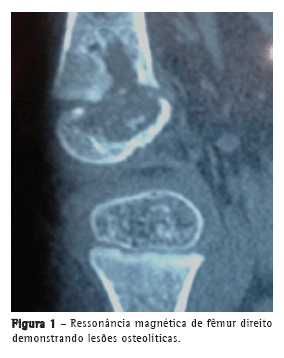

Paciente do sexo feminino com dois anos e quatro meses de idade, proveniente da cidade de São Paulo (SP). Foi vacinada na maternidade com BCG e referia dor na perna direita, com deambulação prejudicada, há 15 dias; foi medicada com anti-inflamatório não hormonal, apresentando melhora, mas com piora duas semanas após a interrupção da medicação. A radiografia do joelho revelou lesão osteolítica na epífise distal do fêmur direito. A ressonância magnética (Figura 1) detectou lesão em epífise distal do fêmur direito, centromedial, com múltiplas áreas de erosão das corticais; havia maior descontinuidade da cortical; ausência de derrame na porção posteroinferior do côndilo femoral medial. Foi medicada por 14 dias com ceftriaxona, sem melhora. A punção biópsia do joelho direito revelou granuloma, sem evidenciação de BAAR. Foi iniciado o tratamento com isoniazida, rifampicina e pirazinamida. A investigação dos pais, irmãos e babás não revelou tuberculose pulmonar ou extrapulmonar. Na admissão ao nosso serviço, alguns dias após o início do tratamento, a paciente apresentava bom estado geral; a única anormalidade no exame físico era edema frio e doloroso à palpação no joelho direito, na porção distal e proximal à tíbia, com incapacidade funcional.